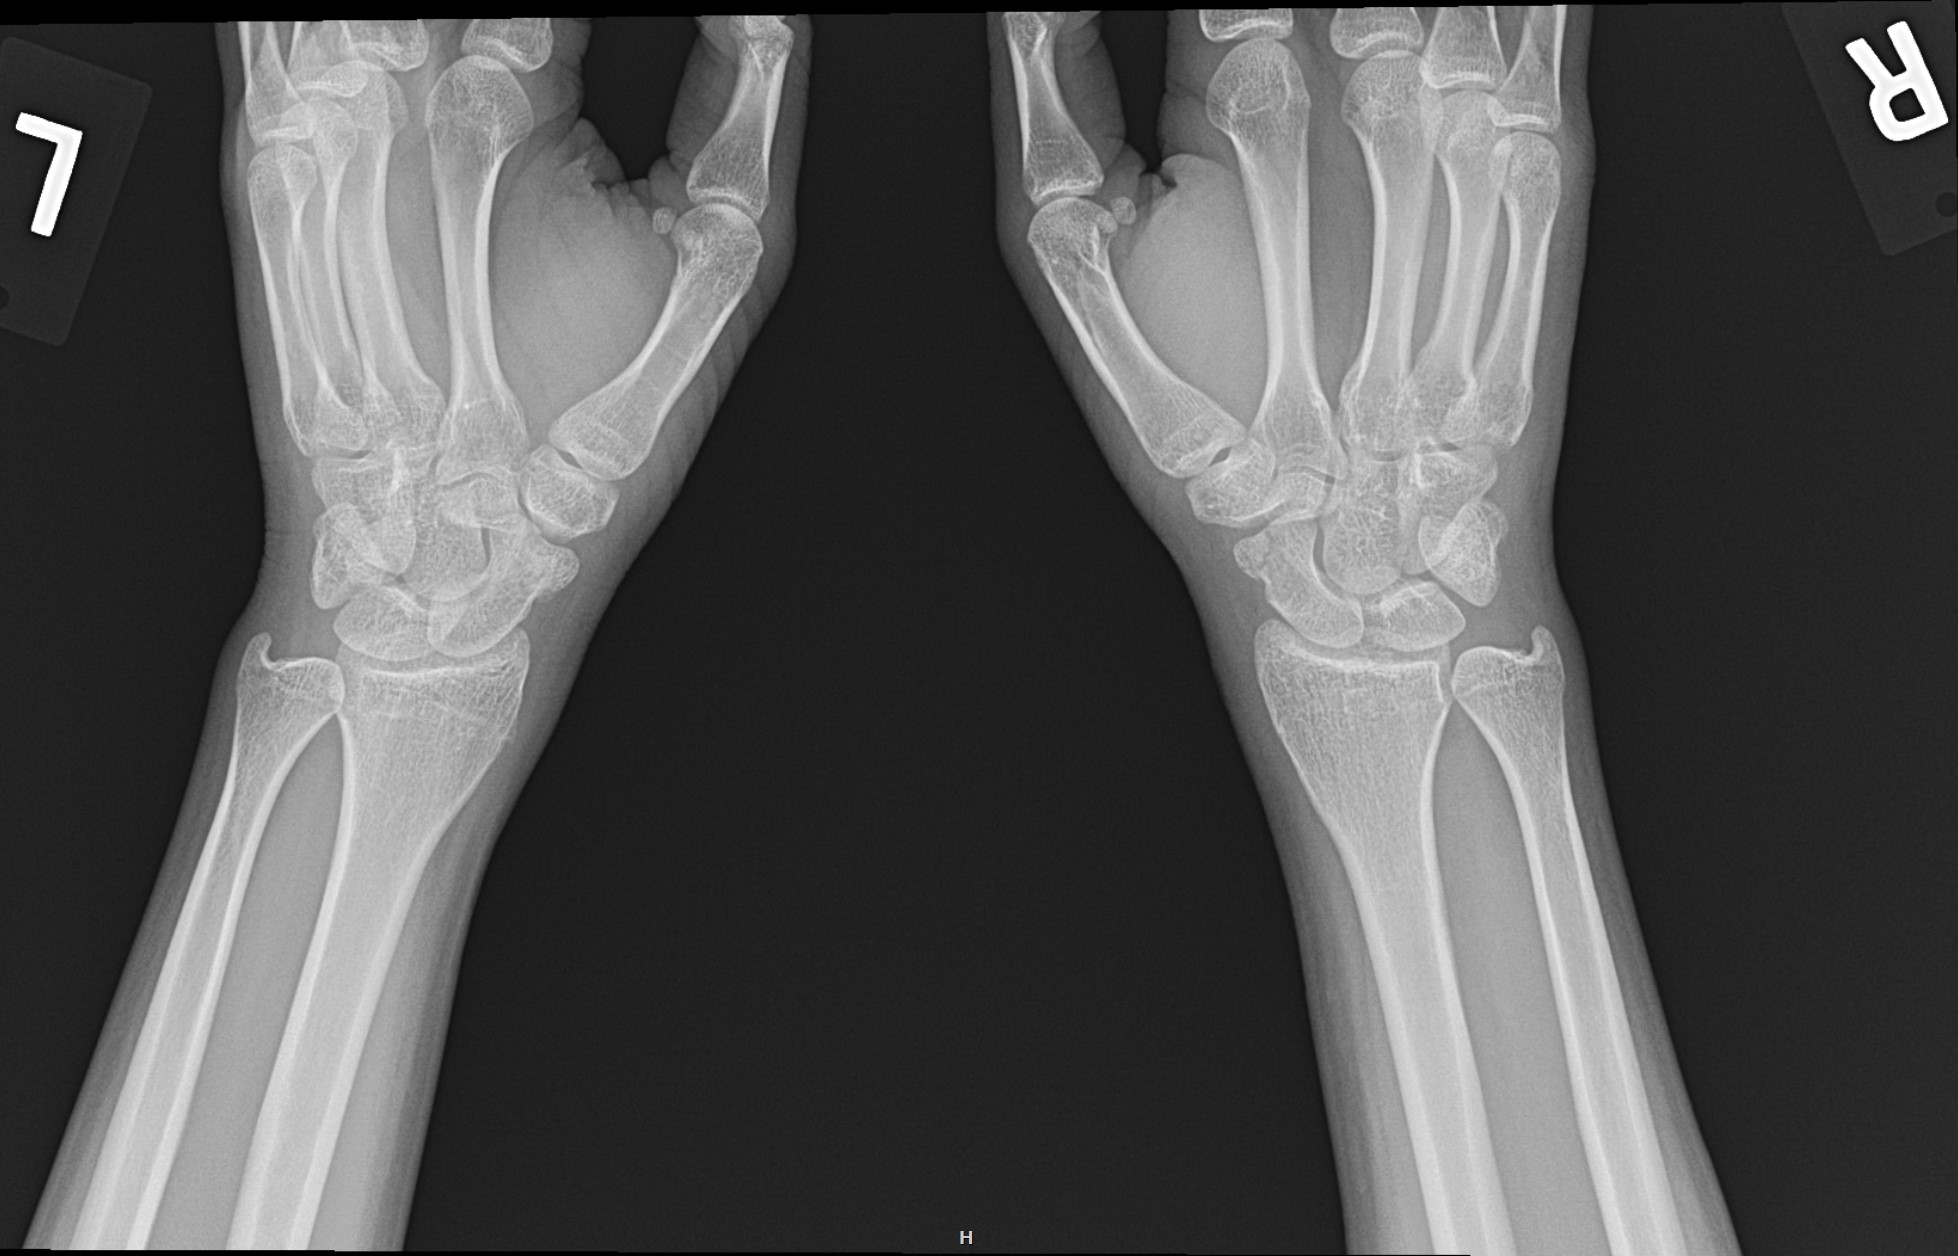

lunotriquetral coalition and fracture